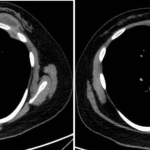

Paciente femenina de 26 años de edad, sin antecedentes patológicos de relevancia, sin dosis de vacuna BCG. Cursa con cuadro clínico de ocho meses de evolución, caracterizado por dolor en región pectoral izquierda intermitente, que se exacerba a la inspiración profunda. En el último mes se palpa masa indurada dolorosa a la palpación a nivel del cuadrante inferior interno de mama izquierda, motivo por el cual se realiza ecografía de partes blandas, donde se observa a nivel retropectoral en íntimo contacto con la parrilla costal imagen hipoecogénica de bordes delimitados, avascular al Doppler color por lo cual se solicita TC de tórax con EV. En ella se observa en topografía del cuarto espacio intercostal, imagen hipodensa con realce periférico tras la administración del contraste que desplaza por efecto de masa el parénquima pulmonar adyacente y se proyecta a la pared torácica anterolateral izquierda; mide 40 mm x 55 mm. Además, se visualiza otra imagen de similares características de base pleural en contacto con el octavo arco costal posterior izquierdo que mide 6 mm x 11 mm.

Cuatro meses posteriores a la PAAF la paciente refiere persistencia de dolor y aumento de tamaño de la masa asociado a eritema en región mamaria, por lo cual se realiza TC de tórax con contraste EV donde se observa imagen hipodensa ya conocida, con realce periférico tras la administración de contraste, con aumento de tamaño y bordes lobulados.

La tomografía computarizada proporciona información más detallada sobre el compromiso extrapulmonar, revelando ganglios linfáticos mediastinales aumentados o nódulos subpleurales que sugieren focos de infección activa.